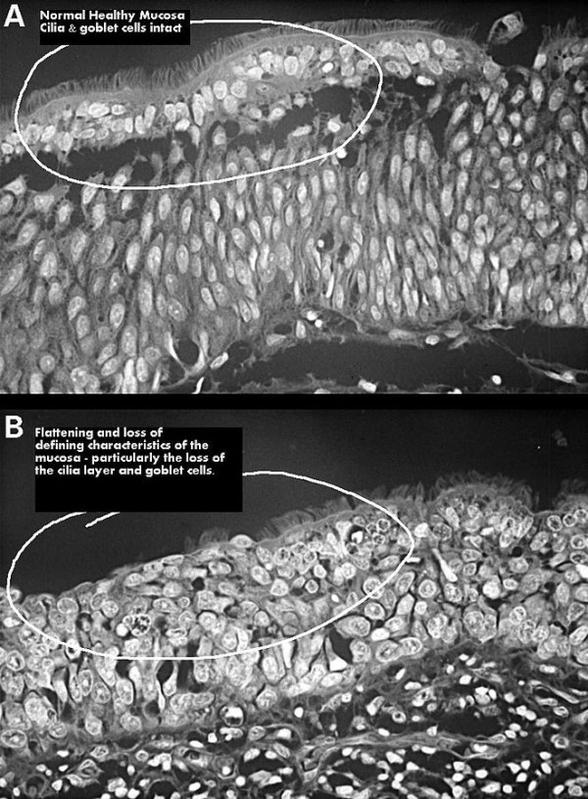

通常来说,移除这部分黏膜并不会造成不良后果。不过,意外总是存在。有的患者在术后,因为黏膜缺损,失去了湿润、清洁空气的能力,鼻腔产生严重干燥感;时间长了,鼻腔内部会发生一系列的病理变化,如静脉炎症、血管萎缩等,这些病理改变,又进一步加重黏膜萎缩,引起黏膜不可逆性损伤,上皮鳞状化生,甚至神经细胞纤维变性等。

(上,正常鼻腔黏膜;下,鼻腔黏膜萎缩;图片来源:wikipedia.org)